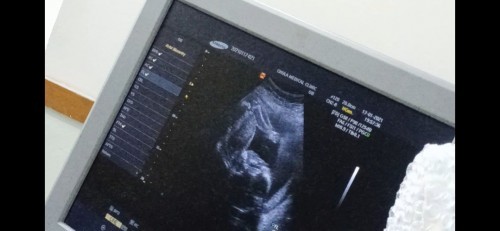

22W หมอบอกว่าน้องนอนหัวทิ้ม #อันตรายไหมคะ #ท้องแรก

เด็กทารกสามารถนอนดิ้นไปมาในน้ำคล่ำได้ทุกทิศทาง ไม่อันตรายอะไรคะ ถ้าจะอันตรายคงจะเป็นสายรกพันคอลูกในท้องละจ้า

วันนี้ตอนไปซาวด์มา ลูกอยู่ไม่นิ่งเลยค่ะพลิกไปมา เดี๋ยวคว่ำเดี๋ยวหงาย น่าจะปกตินะคะถ้าคุณหมอไม่ได้ว่าอะไร

น่าจะไม่เป็นไรนะคะแม่ ปกติน้องก็จะพลิกไปพลิกมาอยู่แล้วค่ะ

บ้านนี้ก็นอนกลับหัวค่ะ อายุครรภ์ 23w4d หมอบอกว่าปกติค่ะ